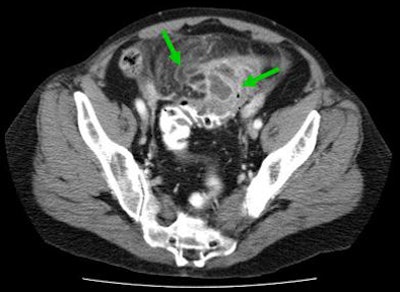

In cases with local complications such as hemorrhage and perforation, both CT and MRI often demonstrate the "lucky hat" sign, which indicates the active migration of omental fat, which drives local inflammation, Rogalla said.

![]() |

| Locally complicated cases with hemorrhage and perforation often reveal a "lucky hat" sign, indicating active migration of omental fat that drives local inflammation. Extracolonic abscess formation indicates stage IIB disease by the Hanson/Stock staging method and stage II by the modified Hinchey system. |